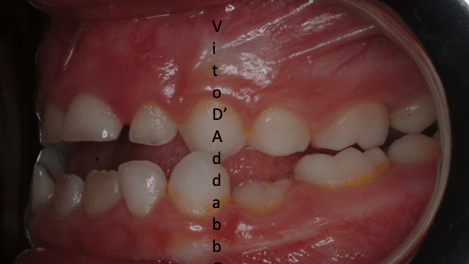

In alcune malocclusioni i denti superiori non coprono adeguatamente quelli inferiori con la presenza in alcuni casi di una beanza fra le due arcate. Questo può essere dovuto ad abitudini viziate come il succhiamento del dito, una deglutizione scorretta, una postura della lingua alterata o un problema scheletrico. In questo esempio il problema è associato ad una terza classe scheletrica.

dopo – fase 2